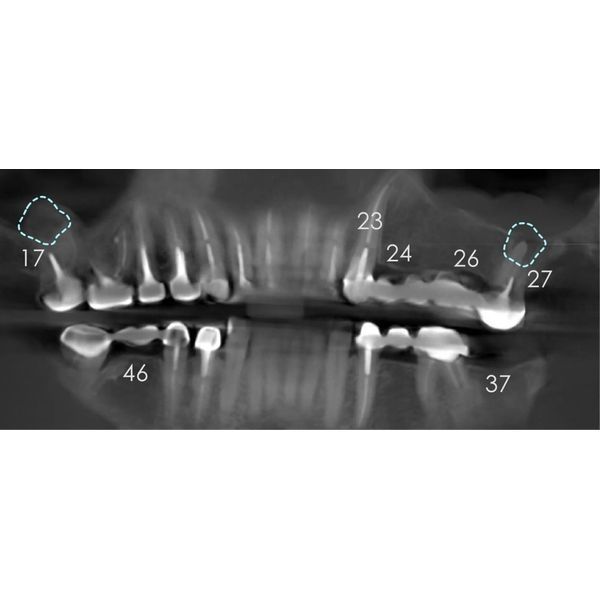

Конусно-лучевая компьютерная томография (КЛКТ) показала:

- очаги разрушения костной ткани в области корней зубов 2.7 и 1.7 — кисты, периодонтит;

- почти идеальное строение левого сустава — суставная головка округлая, с чёткими границами, но суставная щель заметно меньше нормы, т. е. челюсть смещена назад и вверх;

- изменения в правом суставе — деформация суставной головки в сочетании с узурами (эрозиями), участок перестройки костной ткани с «клювовидным» выступом, смещение головки назад;

- однородное заполнение большинства корневых каналов рентгеноконтрастным материалом.